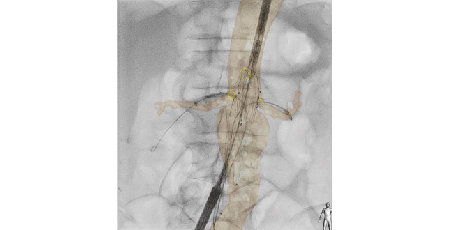

Philips Live Image Guidance

Be sure not to miss out on the latest innovations in imaging techniques for endovascular procedures. Visit our booth to experience: